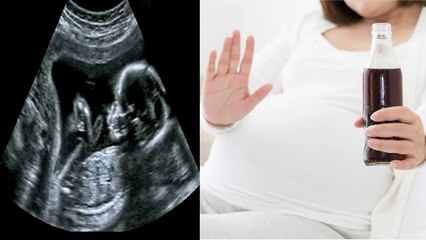

हल्दी केवल एक मसाला ही नहीं बल्कि एक आयुर्वेदिक औषधी भी है। हल्दी के गुणों के बारे में आयुर्वेद में भी बहुत कुछ लिखा गया है। हल्दी में एंटीसेप्टिक, एंटी-फंगल और एंटी-बैक्टेरियल तत्व पाए जाते हैं जो इसे काफी हेल्थी बनाते है, पर कई बारी प्रेगनेंसी के दौरान हल्दी का सेवन करने या हल्दी वाला दोड्ढ पिने के लिए मना किया जाता है, ऐसा क्यों है आइये जानते है br br Turmeric is not only a spice but also an Ayurvedic medicine. A lot has been written in Ayurveda about the properties of turmeric. Antiseptic, anti-fungal and anti-bacterial elements are found in turmeric which make it very healthy, but many times it is forbidden to consume turmeric or drink turmeric powder during pregnancy, let us know why. br br #PregnancyMeHaldiWalaDoodhPeenaChahiyeYaNahi, #PregnancyMeHaldiWalaDoodhPineSeKyaHotaHai, #PregnancyMeHAldiValaDoddhPiSakteHAibr ~HT.97~PR.266~ED.